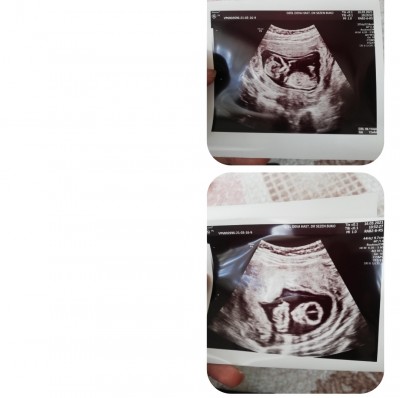

Bi tahmin teyzeleri 12+6 da cekilmiş foto

Gebelik haftası 13 haftalık

Kapatılma nedeni: Cinsiyet tahminlerini sol üst köşeden konu dışı sohbetten sorabilirsiniz